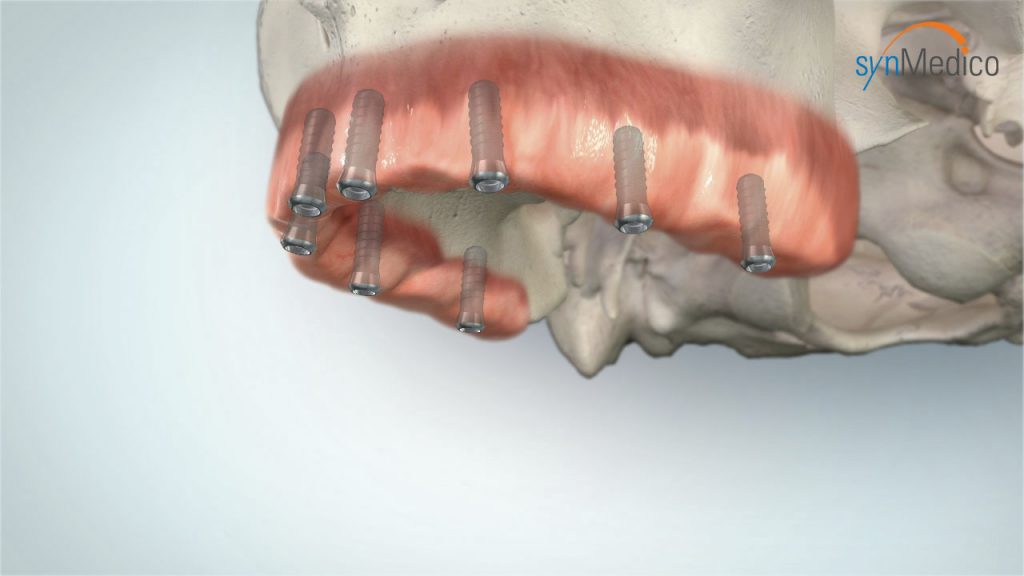

Zahnloser Kiefer

Auch ein zahnloser Kiefer kann mit Implantaten komfortabel versorgt werden. Bereits bestehender Zahnersatz gewinnt auf Implantaten neuen, verbesserten Halt. Das Gesichtsprofil bleibt erhalten, Essen und Lachen ist kein Problem mehr, die Aussprache wird deutlicher. Der Patient kann sich auf einen wirklich funktionierenden Zahnersatz verlassen.